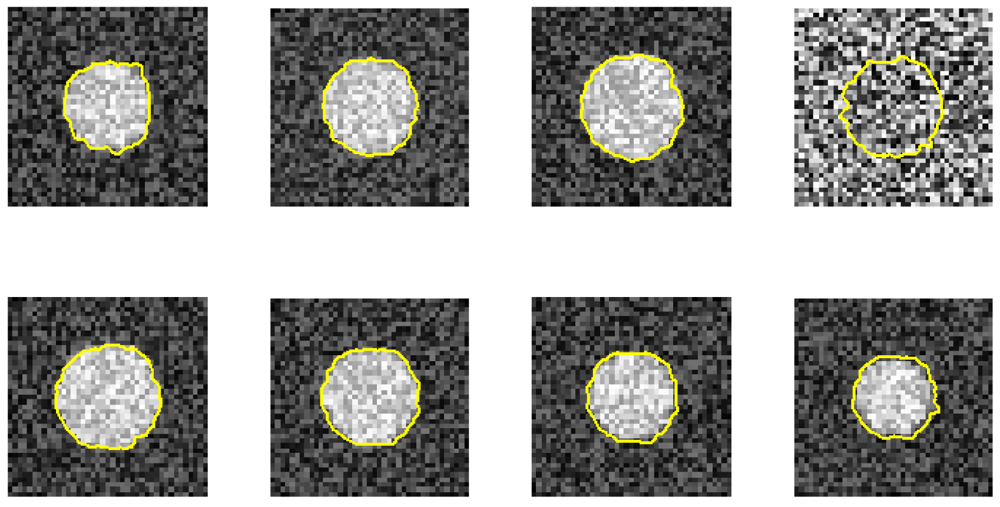

Furthermore, we demonstrate the ability of the proposed method when one image is ruined. Figures 7 and 8 use the same eight phantom images (SNR = 14 dB), and their boundary detection results differ on the ruined image. The traditional DP has no knowledge about the third direction, and it fails to detect the boundary if the image is ruined. However, our method shows its robustness against strong noise.